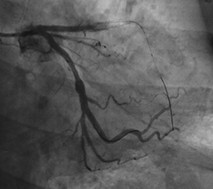

支架内出现狭窄,考虑到反复出现支架内狭窄,建议外科治疗,在与患者及家属沟通后选择介入治疗。选择6F的EBU3.5指引导管,应用runthrough指引导丝到达病变远端后应用2.5x15mm的球囊以12atm扩张,重复造影显示前降支血流消失(图2)。

图2 前降支中段后无血流,回旋支正常显影

患者有轻微胸闷,血流动力学尚稳定。立即往冠脉内给予硝酸甘油100~200ug合心爽100ug多次,重复造影仍然没有血流;支架内应用3x10atm的切割球囊在支架内扩张1次,扩张压力12~16atm,在支架边缘应用2.5的球囊低压扩张,也没有好转;沿前降支导丝送入微导管到达病变远端,抽出导丝,沿微导管向冠脉内给予硝酸甘油100~200ug,合心爽100ug多次,仍无明显好转。进行血管内超声(图3)。